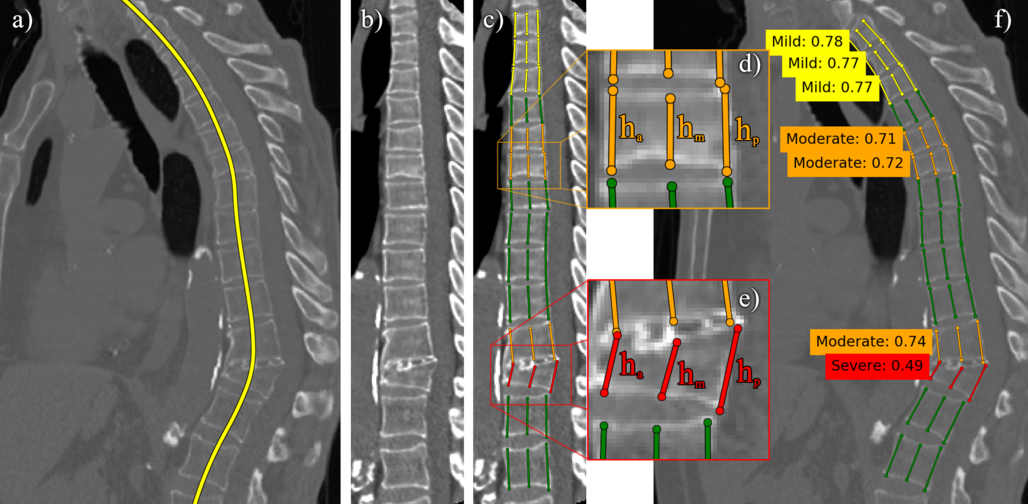

Refer to caption

Figure 6: Examples on which our model (yellow) performs poorly. Note the variability of the expert annotation (red).